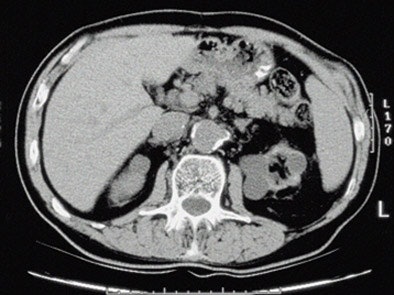

| Top to bottom: Indented kidneys with cysts typical of ESRD, but not 'SICK,' seen in a 61-year-old patient. All patients were imaged within three months of ESRD diagnosis and the beginning of dialysis, and yielded only subtle CT findings in most of them. All images courtesy of Lauren Brubaker. |

"We developed the acronym 'SICK' to indicate bilaterally small, indented, and calcified kidneys," she said. "In terms of radiological findings, as you would expect, we found small, smooth kidneys in 65% of our ESRD population. Other typical ESRD patterns were small kidneys with cysts, as well as kidneys with so many cysts they are causing indentations or scars within the kidneys. Contour was assessed for calcification through scars, as well as calcifications for size and location."